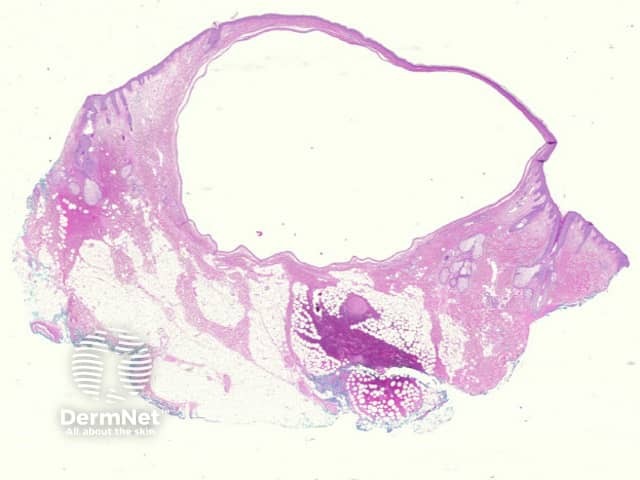

A cystic space occupies the dermis which may be unilocular (figure 1) or multilocular. The cystic space is lined by a bilaminar epithelium which has on its inner portion cells which are columnar, eosinophilic and show prominent luminal blebbing (‘apocrine snouts’) (figures 2 and 3).

Epithelial proliferations may be seen within the cyst.

Figure 1